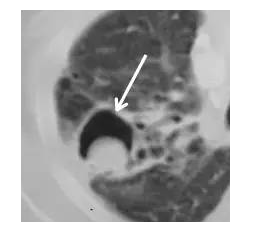

空气新月征

空腔内生长出肿块,从而形成空气新月征,提示侵袭性曲霉感染,也可见于肺癌、结核、Wegener肉芽肿等。